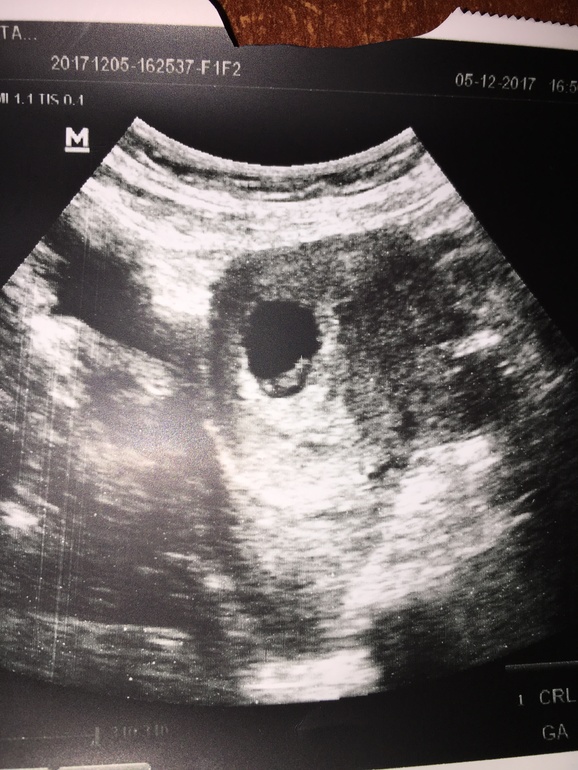

лодный мешок узи

Плодный мешок узи 87 фото